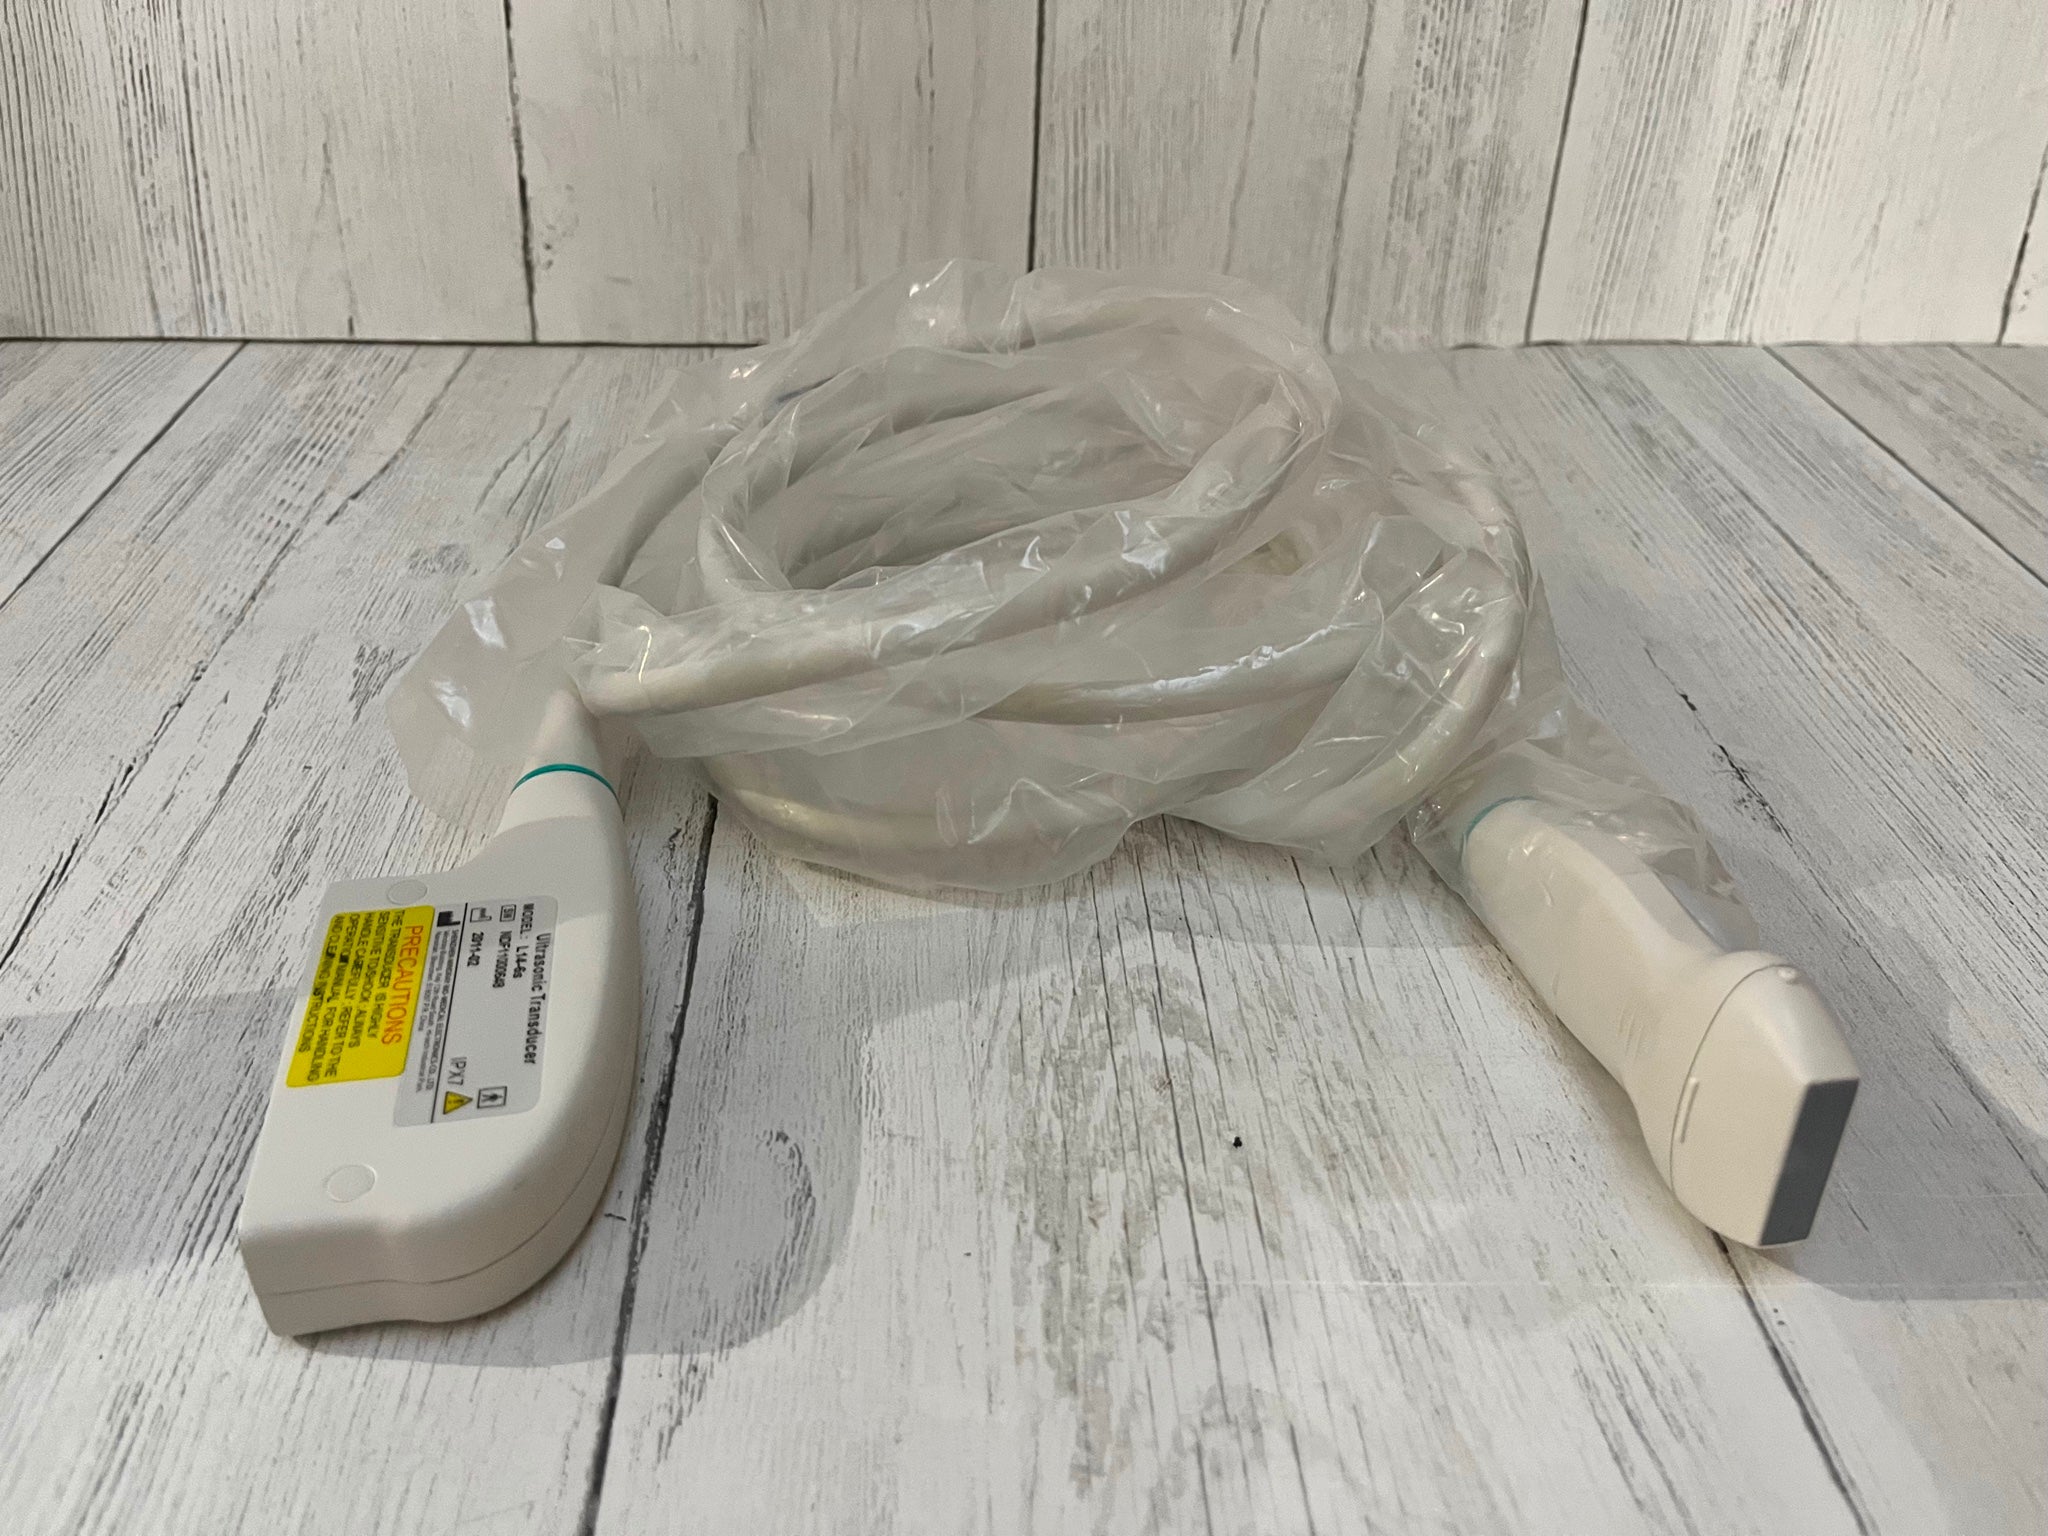

Model: RUS-6000A

Brand: Carejoy

![Digital 3D Ultrasound Scanner Convex + Linear 2Probe/Transducers +Oximeter [DHL] 190891435651 DIAGNOSTIC ULTRASOUND MACHINES FOR SALE](http://ultraultrasound.com/cdn/shop/products/s-l1600_55eda9f8-0657-42e5-b08f-fb450561b305.jpg?v=1571451481&width=562)

![Digital 3D Ultrasound Scanner Convex + Linear 2Probe/Transducers +Oximeter [DHL] 190891435651 DIAGNOSTIC ULTRASOUND MACHINES FOR SALE](http://ultraultrasound.com/cdn/shop/products/s-l1600_a77dd9e6-c605-475e-b3f1-9f86fc93dbb9.jpg?v=1571451481&width=800)

![Digital 3D Ultrasound Scanner Convex + Linear 2Probe/Transducers +Oximeter [DHL] 190891435651 DIAGNOSTIC ULTRASOUND MACHINES FOR SALE](http://ultraultrasound.com/cdn/shop/products/s-l1600_99c50fa2-36fe-4a5b-bcf7-6ee7a0bac49b.jpg?v=1571451481&width=800)

![Digital 3D Ultrasound Scanner Convex + Linear 2Probe/Transducers +Oximeter [DHL] 190891435651 DIAGNOSTIC ULTRASOUND MACHINES FOR SALE](http://ultraultrasound.com/cdn/shop/products/s-l1600_d50ffb69-35d9-4e4d-a2f5-fd83f8b897dc.jpg?v=1571451481&width=500)

![Digital 3D Ultrasound Scanner Convex + Linear 2Probe/Transducers +Oximeter [DHL] 190891435651 DIAGNOSTIC ULTRASOUND MACHINES FOR SALE](http://ultraultrasound.com/cdn/shop/products/s-l1600_e2646f33-3bdd-4c03-a93f-5ecff438ba60.jpg?v=1571451481&width=500)

![Digital 3D Ultrasound Scanner Convex + Linear 2Probe/Transducers +Oximeter [DHL] 190891435651 DIAGNOSTIC ULTRASOUND MACHINES FOR SALE](http://ultraultrasound.com/cdn/shop/products/s-l1600_73c5e27c-235b-4093-a5c8-da4c1fd871e6.jpg?v=1571451481&width=500)

![Digital 3D Ultrasound Scanner Convex + Linear 2Probe/Transducers +Oximeter [DHL] 190891435651 DIAGNOSTIC ULTRASOUND MACHINES FOR SALE](http://ultraultrasound.com/cdn/shop/products/s-l1600_65d7ce40-ffb2-4c36-b75e-a0711be5b0e9.jpg?v=1571451481&width=800)

![Digital 3D Ultrasound Scanner Convex + Linear 2Probe/Transducers +Oximeter [DHL] 190891435651 DIAGNOSTIC ULTRASOUND MACHINES FOR SALE](http://ultraultrasound.com/cdn/shop/products/s-l1600_76b8761b-3e35-42b3-8ef6-77d9bb2d1b38.jpg?v=1571451481&width=800)

![Digital 3D Ultrasound Scanner Convex + Linear 2Probe/Transducers +Oximeter [DHL] 190891435651 DIAGNOSTIC ULTRASOUND MACHINES FOR SALE](http://ultraultrasound.com/cdn/shop/products/s-l1600_cfe20fc7-5697-4c1a-8391-2580b856e6e0.jpg?v=1571451481&width=787)

![Digital 3D Ultrasound Scanner Convex + Linear 2Probe/Transducers +Oximeter [DHL] 190891435651 DIAGNOSTIC ULTRASOUND MACHINES FOR SALE](http://ultraultrasound.com/cdn/shop/products/s-l1600_358e66eb-4359-4c64-b1e8-a9dcd0e814ad.jpg?v=1571451481&width=787)

![Digital 3D Ultrasound Scanner Convex + Linear 2Probe/Transducers +Oximeter [DHL] 190891435651 DIAGNOSTIC ULTRASOUND MACHINES FOR SALE](http://ultraultrasound.com/cdn/shop/products/s-l1600_30e9b73a-963b-405f-aac6-1e35df6dd5a5.jpg?v=1571451481&width=500)

![Digital 3D Ultrasound Scanner Convex + Linear 2Probe/Transducers +Oximeter [DHL] 190891435651 DIAGNOSTIC ULTRASOUND MACHINES FOR SALE](http://ultraultrasound.com/cdn/shop/products/s-l1600_5f5dd2f5-1278-4642-992d-76ca0ab3df32.jpg?v=1571451481&width=800)